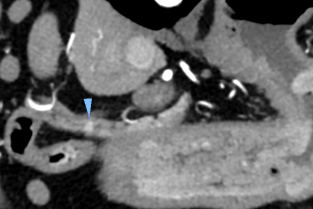

La deuxième journée de cette 3ème édition des Journées annuelles du GEO sera consacrée aux tumeurs du système endocrine du chien et du chat, permettant ainsi d'allier endocrinologie et oncologie. L'accent sera ainsi mis sur les tumeurs thyroïdiennes, parathyroïdiennes, hypophysaires, surrénaliennes, et du pancréas endocrine.

- aborder les tumeurs surrénaliennes, bénignes ou malignes, sécrétantes ou non sécrétantes, que ce soit de cortisol, de catécholamines ou d'aldostérone ;

- mener une démarche diagnostique face à la découverte d'un fortuitome surrénalien ;